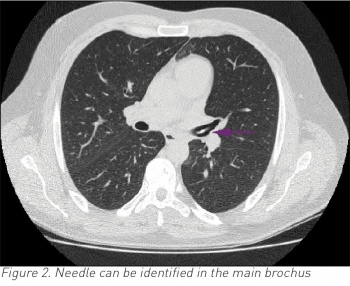

A CT thorax was performed to further evaluate for cause of haemoptysis. Imaging showed a needle in the left main bronchus entering the main pulmonary vein (see Figures 1 and 2).